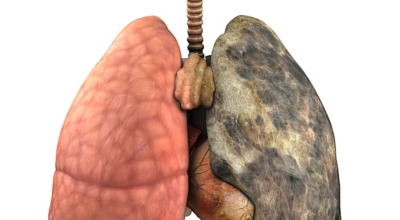

폐에 발생한 악성 종양을 말하며, 오랜 기간 흡연해온 남성에게서 발병률이 높습니다. 하지만 최근에는 다양한 환경적 요인과 간접흡연의 영향으로 흡연하지 않는 여성에게서도 많이 발생하고 있답니다. 증상을 느껴 병원을 찾았을 때는 이미 수술하기엔 늦은 경우가 많아 사망률이 매우 높은 암입니다. 폐 자체에서 생기거나 다른 장기에서 발생한 암이 폐로 전이되어 나타나기도 하며, 특별한 초기 증상이 없는 경우가 많습니다. 암이 진행된 후에도 일반적인 감기 증상인 기침과 가래 외에 뚜렷한 증상이 나타나지 않아, 증상만으로는 진단이 쉽지 않습니다.

폐암의 공통적인 위험 요소로 손꼽히는 이유 중 하나가 바로 흡연입니다. 흡연자는 비흡연자에 비해 폐암 발병 확률이 수십 배나 높다고 하며, 흡연을 해온 기간이 길수록 그 위험은 더욱 커집니다. 하지만 흡연자라 하더라도 금연을 하면 폐암 발병 확률이 빠르게 낮아진다고 하니, 폐암이 걱정되신다면 무엇보다 먼저 금연이 필수입니다.